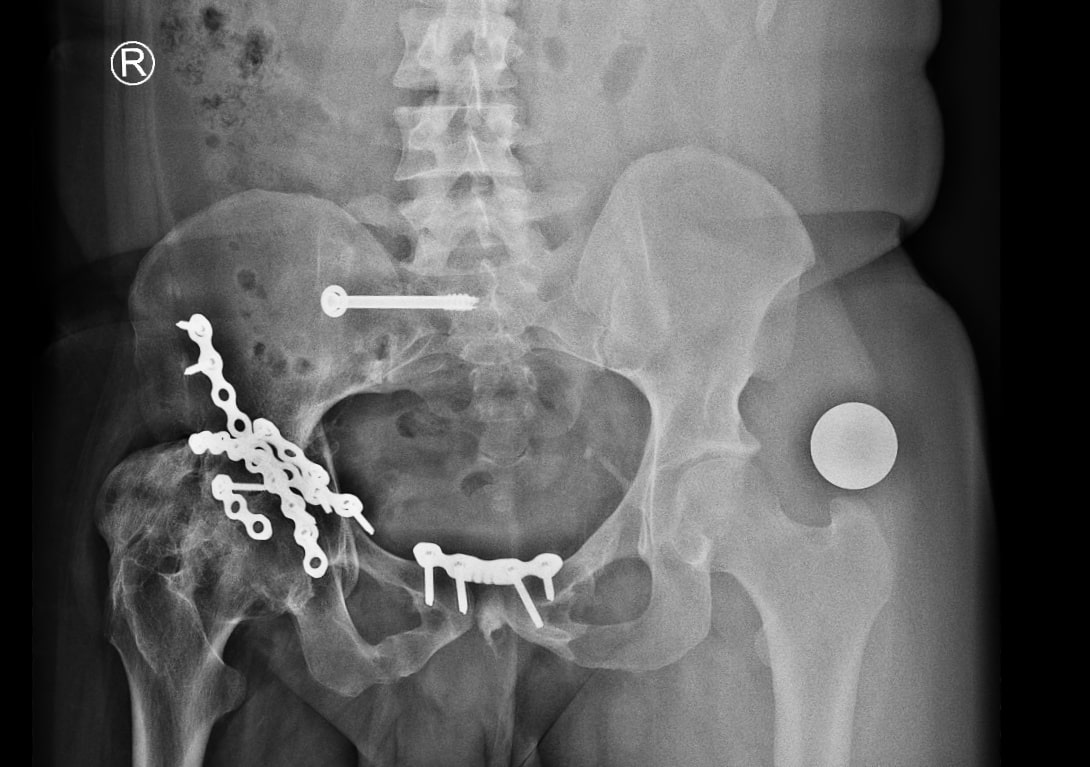

Radiographs demonstrated malunited anterior and posterior columns with retained implants, medial acetabular migration, and massive mature HO bridging the acetabulum and proximal femur (Brooker grade IV)(Fig 1). CT scan showed mal united fracture of both columns, heterotopic mass extending superior, anterior and posterior to the right proximal femur causing extra articular ankylosis(Fig 2 a). There also was intra articular ankylosis with trabeculae crossing the hip joint posteriorly fusing with the acetabulum. There was severe protrusio with intact medial wall. CT angiography superimposed images revealed the external iliac vessels closely abutting but not encased by the HO(Fig 2 b).

Postoperative Course

Radiographs demonstrated satisfactory medial wall reconstruction, restored offset, and removal of impinging HO(Fig 5). The patient commenced weight-bearing on postoperative day 1. HO prophylaxis with indomethacin 25 mg thrice daily was prescribed for 6 weeks.

At 6 weeks, he was independently mobile and able to don his prosthesis unaided(Fig 6). At 1 year, he remained pain-free, returned to motorcycling, and radiographs revealed minimal (Brooker grade1) recurrence of HO.